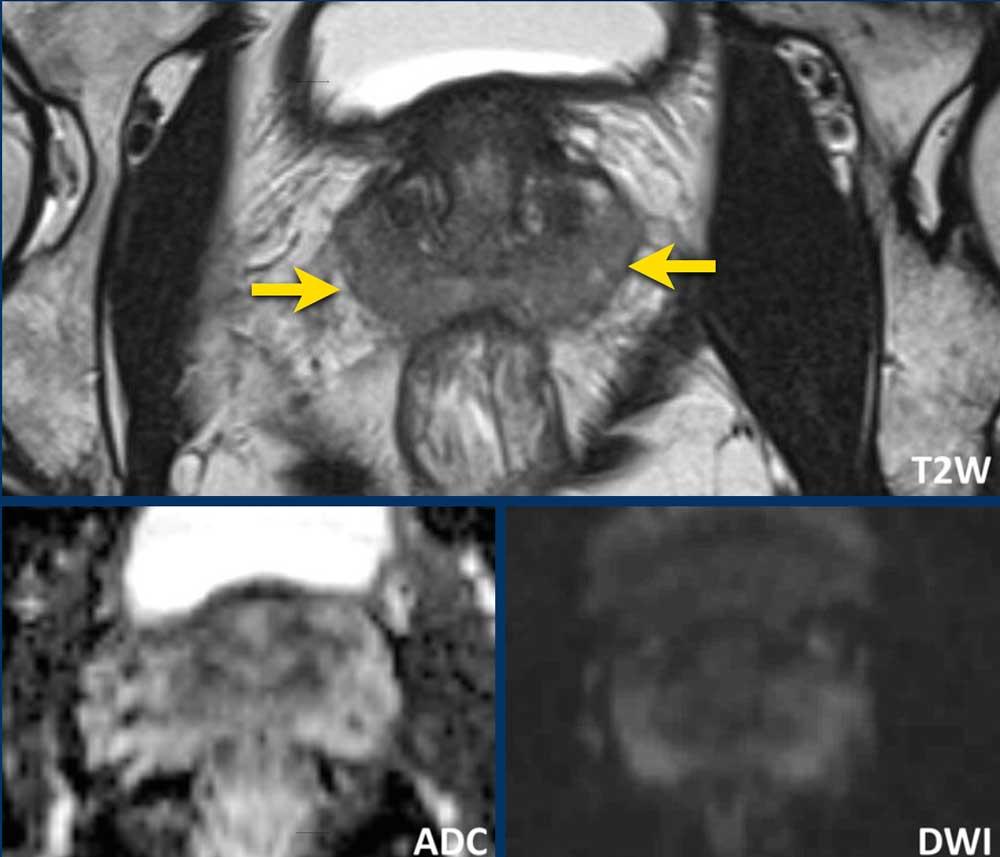

Hình ảnh

Tổn thương 27 mm nằm ở phía trước đỉnh vùng chuyển tiếp, với hình ảnh “than bị xóa”.

Tổn thương này tương ứng với một vùng khuếch tán hạn chế có hình dạng giọt nước.

Tổn thương được xếp loại PI-RADS mức 5.

Sinh thiết dưới hướng dẫn kết hợp MRI/Siêu âm cho kết quả Gleason 3+4.